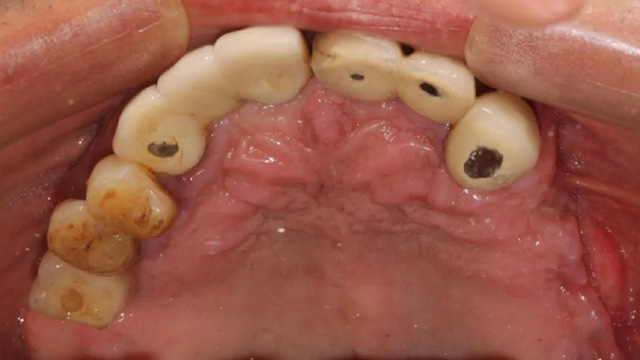

吳叔叔當時的口腔情況

“上面種了4顆,斷了兩顆,脫落1顆,只有1顆能用,下面有一顆牙冠脫落,另一顆有種植體周圍炎,有明顯的骨吸收。”吳叔叔剩下的天然牙也不好,做了幾處修復,之前的牙冠修復用的都是烤瓷牙,有好幾顆磨損嚴重露出了金屬。由于存在缺牙、不良修復體等情況,口腔整體咬合紊亂,進食很困難。